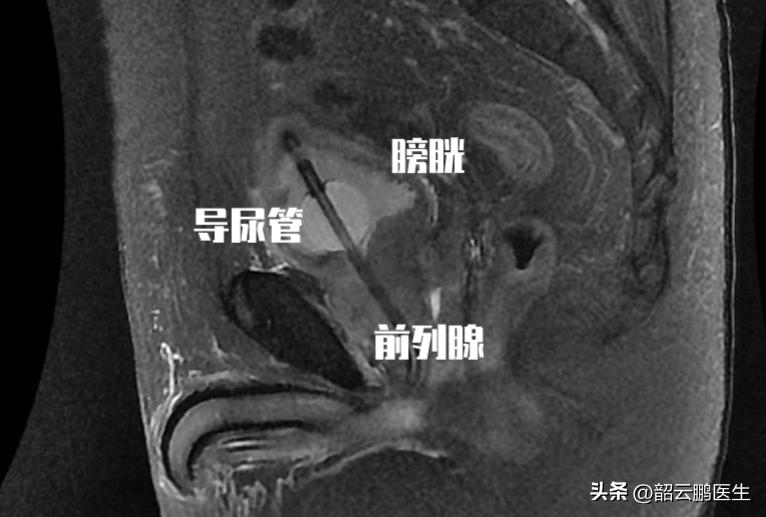

坦索罗辛是一种选择性 α1肾上腺素受体阻滞剂 ,之所以应用在前列腺增生的患者中,它的主要作用机制是 选择性阻断前列腺、尿道和膀胱颈中的α1肾上腺素受体,松弛前列腺、尿道和膀胱颈平滑肌,从而改善良性前列腺增生症所致的尿急、尿频和排尿困难等症状。

前列腺增生在老年人的发病率最高,所以 针对排尿问题应用坦索罗辛的人也以老年人为主 。虽然坦索罗辛是选择性α1肾上腺素受体阻滞剂,但是它之所以出现并发症,也是由于α1肾上腺素受体除了分布在肾脏、前列腺、膀胱括约肌外,还在 脑、心脏、血管等,其在血管平滑肌激动后的主要效应为血管收缩。

使用坦索罗辛阻断后, 血管舒张,导致外周血容量增加,血压下降,在体位发生变化时可能会诱发低血压。 所以老年人在用药初期,除了需要 按照饭后服药外 ,最为关键的就是需要 监测血压波动 ,同时 防止摔倒的要求更为迫切 ,尤其是意识丧失情况下的摔倒风险更高。